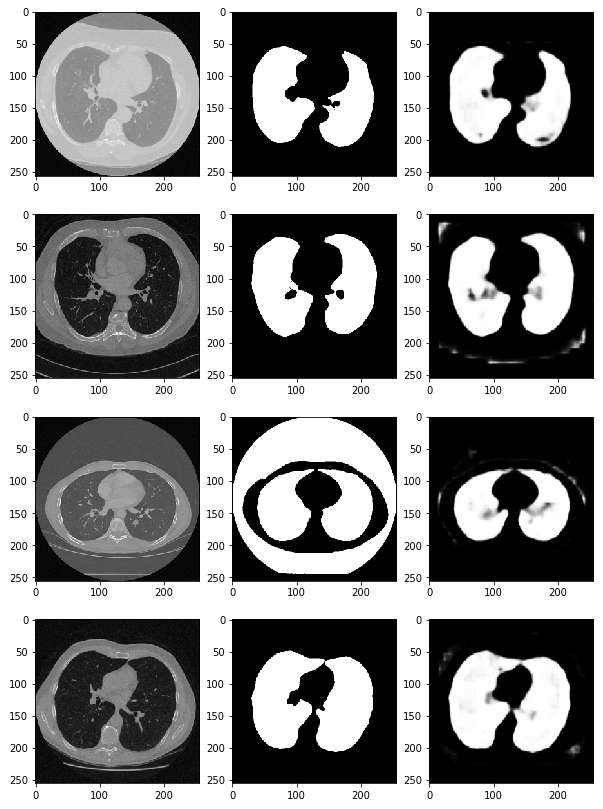

preds = model.predict(x_val) # predict 함수를 통해 (x_val) 검증한다

fig, ax = plt.subplots(len(x_val), 3, figsize=(10, 100))

for i, pred in enumerate(preds):

ax[i, 0].imshow(x_val[i].squeeze(), cmap='gray') # 첫 번째 열에는 CT 데이터(x_val[i])를 삽입

ax[i, 1].imshow(y_val[i].squeeze(), cmap='gray') # 두 번째 열에는 정답 데이터를 넣는다.

ax[i, 2].imshow(pred.squeeze(), cmap='gray') # 세 번째 열에는 우리가 예측한 결과값을 그려본다.

# 이러한 딥러닝을 활용하여 산소의 수치, 적혈구, 백혈구의 농도 등 수치적 데이터를 가지고 예측하는 방법도 존재함.